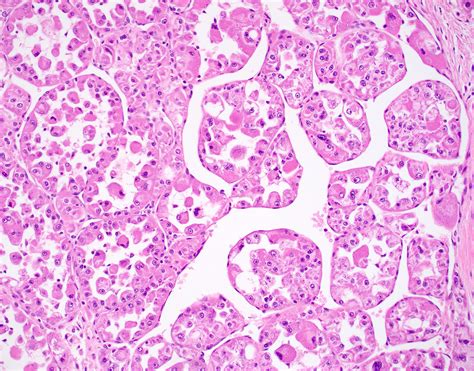

ASPS is a type of soft tissue sarcoma that originates from the mesenchymal cells, which are responsible for the formation of connective tissues. The disease is named for its distinctive alveolar pattern under the microscope, which resembles the structure of lung alveoli. This pattern is a key diagnostic feature that helps differentiate ASPS from other types of sarcomas.

Histopathological examination reveals the characteristic alveolar pattern of ASPS, which is essential for a definitive diagnosis. Additionally, immunohistochemical staining and molecular genetic testing can provide further confirmation.